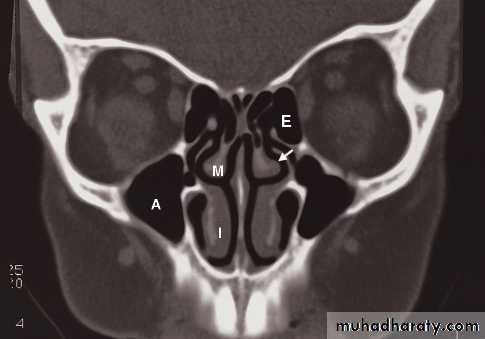

• However, CT is often the preferred technique in sinus disease

• On plain radiographs the normal sinuses are transradiant because they contain air.• Plain films have a role in showing mucosal thickening, fluid levels, bone destruction and fractures.